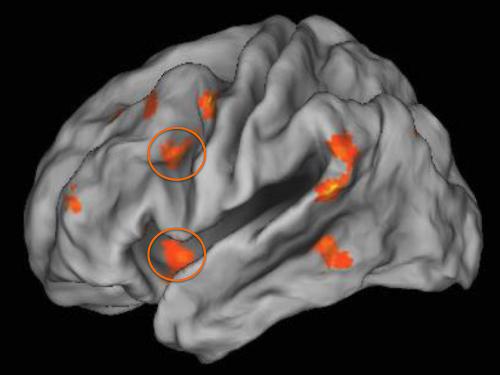

Starea de sărăcie din copilărie are impact asupra implicării celor două regiuni ale cortexului pre-frontal (cercurile oranj din imaginea de mai sus) în reglarea emoţională.

S-a descoperit că subiecţii testaţi care aveau familii cu venituri mai mici, manifestau – ca adulţi – o activitate mărită la nivelul amigdalei, zonă cerebrală cu rol în emoţiile negative şi în spaimă. Aceste persoane manifestau o activitate mai mică în zona cortexului prefrontal, zona cerebrală de reglare a emoţiilor negative.

Disfuncţiile amigdalei şi ale cortexului prefrontal au fost asociate de către autori cu problemele de dispoziţie psihică, incluzând depresiile, anxietatea, impulsivitatea agresivă şi reacţiile la abuzurile suferite.

Utilizând imagistica de rezonanţă magnetică, a fost evaluată activitatea cerebrală a participanţilor înregistrată la executarea unei sarcini care implica reglare emoţională. Folosind o strategie de rezolvare cognitivă, li s-a cerut subiecţilor să încerce să supreseze emoţiile negative înregistrate la vizionarea unor imagini.